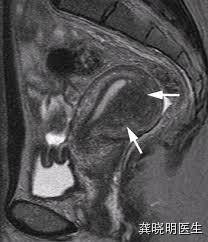

核磁共振检查也会有类似的发现,可以发现肌层有明显的增厚和结构紊乱,在核磁共振上更加明显。

肌腺症在子宫内部若是局部形成一个象肌瘤一样的结节,在超声上可能会比较局限,看起来象是一个肌瘤,但是通常边界不如肌瘤清楚,绝大多数超声认为的腺肌瘤其实都是腺肌症的表现,这在核磁共振检查上更清晰。